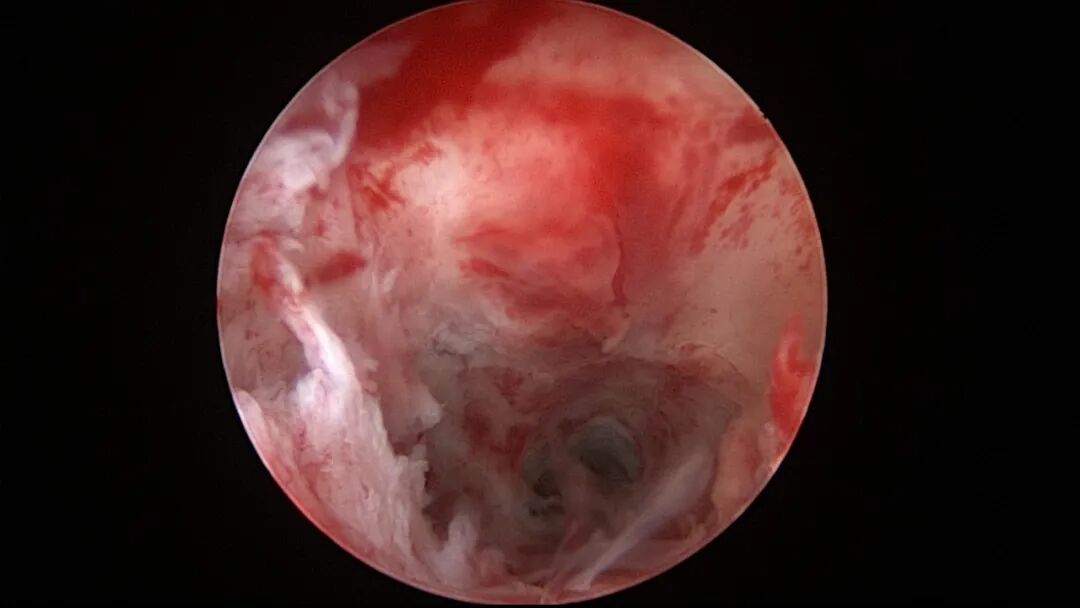

第八次宫腔镜:2025年7月宫腔镜二探取球囊,宫腔形态正常,双侧输卵管开口可见,内膜薄,片状充血。球囊在宫腔具有持续塑形作用,分粘术中没有显露的右侧输卵管开口已自我修复。